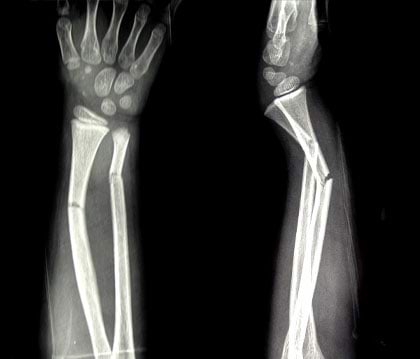

Murdunud käeluu röntgenpilt

Just selliste röntgenpiltide järgi oskavad arstid murdunud käeluu jälle õigesti kokku panna.